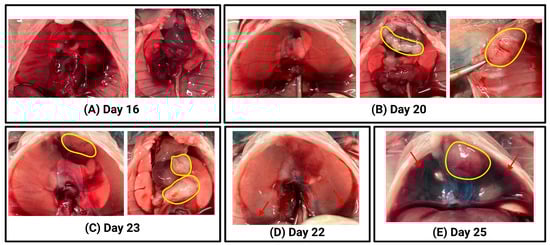

4.3. Macroscopic Examination Confirms Tumour Development in Injected Mice

4.4. Histological Analysis Demonstrates Progressive Tumour Growth